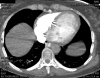

Video 2 - Echokardiograficky byla zjištěna těžká dysfunkce dilatační levé komory s nezvětšenou pravou komorou.Pro nejasnou příčinu zástavy jsme provedli i vyšetření výpočetní tomografií (CT), které vyloučilo plicní embolizaci (série 1 - soubory na konci článku). V den přijetí při přetrvávající oběhové nestabilitě byla nemocná opakovaně defibrilována pro fibrilaci komor se stabilizací rytmu po podání amiodaronu a mesocainu. Dle hemodynamických měření se jednalo o těžký kombinovaný šok. Vstupní laboratorní vyšetření bylo bez větších pozoruhodností. Posléze jsme doplnili anamnézu od příbuzných a zjistili, že pacientka užila do dvou hodin před srdeční zástavou první tabletu amoxicilinu na lehký respirační infekt. Při nevýtěžnosti vstupních vyšetření a nových anamnestických informacích jsme doplnili 14 hodin po kolapsu vyšetření koncentrace tryptázy v séru, která byla extrémně zvýšena (tabulka 2), což nás vedlo k podezření na anafylaxi.